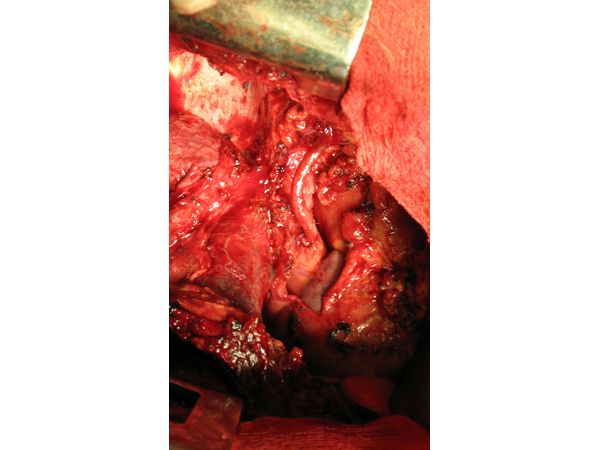

28 августа 2007 года пациенту рассекли грудную стенку по V межреберью. В плевральной полости сращений не было. В верхнем средостении выявили каменистое скопление, которое охватывало верхнюю полую вену, распространялось на корень правого лёгкого и сдавливало правую лёгочную артерию и вену. Образование плотно прилегало к стенке верхней полой вены и при отделении обильно кровоточило.

После вскрытия перикарда выяснилось, что непарная вена и ветви верхней полой вены значительно увеличены. Биопсия позволила поставить точный диагноз — идиопатический фиброматоз.

Учитывая распространённость процесса, приняли решение выполнить декомпрессию верхней полой вены с помощью шунтирования. Операция проводилась вместе с сосудистым хирургом. В качестве шунта был взят участок большой подкожной вены. Им соединили безымянную и кавальную вену ниже образовавшейся опухоли (рис. 5). После пуска кровотока шунтирующая вена хорошо заполнялась кровью. Участки соединения (анастомозы) проходимы и герметичны.